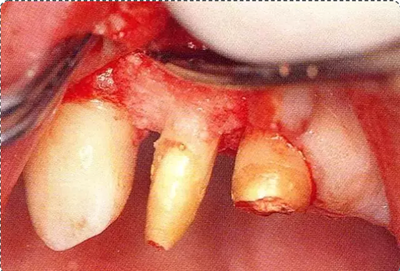

圖10-1

遠中部有8mm的牙周袋。上頜前牙部等需要考慮審美性的部位進行GTR法,但也可能會出現(xiàn)齦瓣壞死導致牙齦乳頭喪失,反而導致審美性變差的情況。

圖10-3  考慮到審美性,應用牙齦乳頭保存術(Papilla preservation technique),進行了自體骨移植。